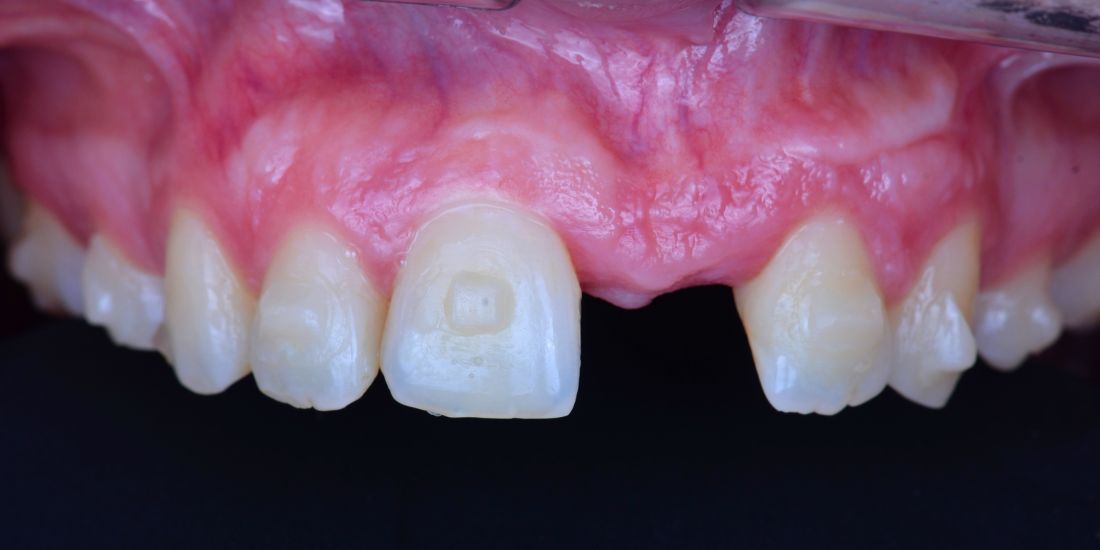

Metamorfoza WDC:

koncepcja minimally invasive preparation

Opis metamorfozy